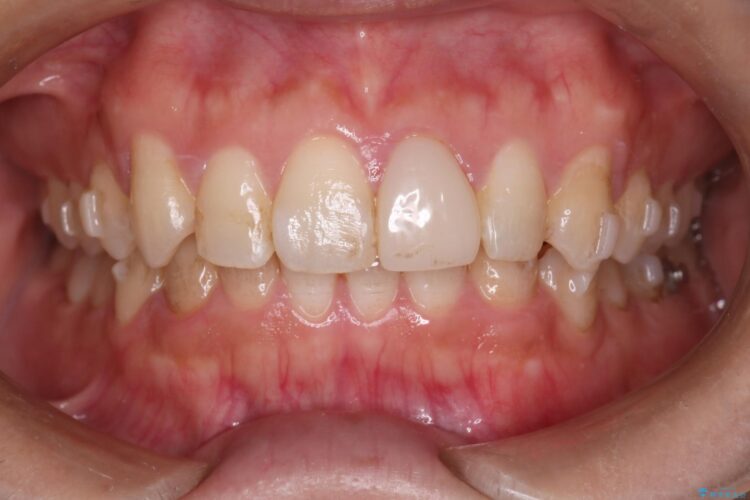

インビザライン矯正により、前歯のガタつきが改善されました。

また、左上1番目の前歯はセラミックをご希望されたため、被せ物の治療を行いとても美しい前歯となりました。